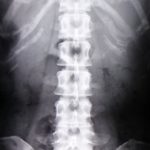

Q4,老化や骨の変形で痛みが起きる

Q5,画像検査で痛みの原因がわかる

昔は上記のようなことが常識とされていましたが、研究が進むにつれ矛盾だらけで説明がつかないため、考え方が変わったのです。